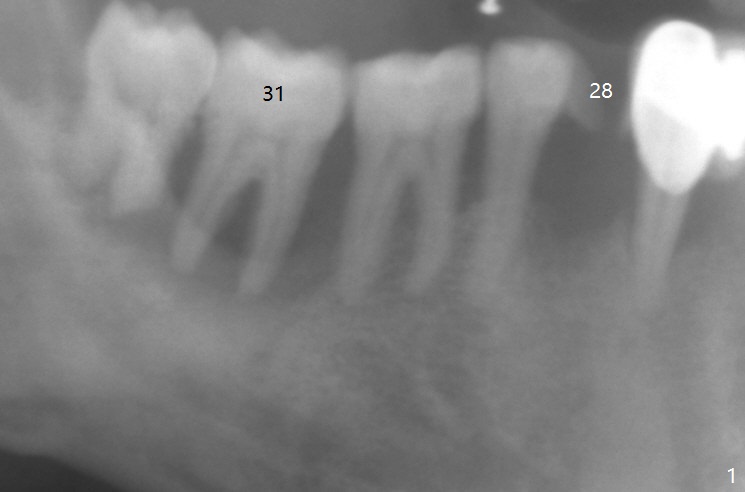

After having upper implants placed (9-11, 15 UR), a 46-year-old man requests taking care of the loose tooth at #31 and the missing tooth #28 next (Fig.1). Bone height is limited at #31 (Fig.2); if hemorrhage and pain are controllable, an extra wide Bicon implant will be placed. In the posterior region with unfavorable implant crown ratio, there is less likelihood to separate Bicon abutment from its implant because of friction mechanism. But 3-5 mm stoppers and drills are from another implant system (regular and wide kits). CT may be taken intraop if needed. PRF membranes will be used to close the large socket opening with a hole for abutment penetration if instructed. Autoclave a needle with endo syringe to inject PRF liquid into the tissue to facilitate tissue healing.